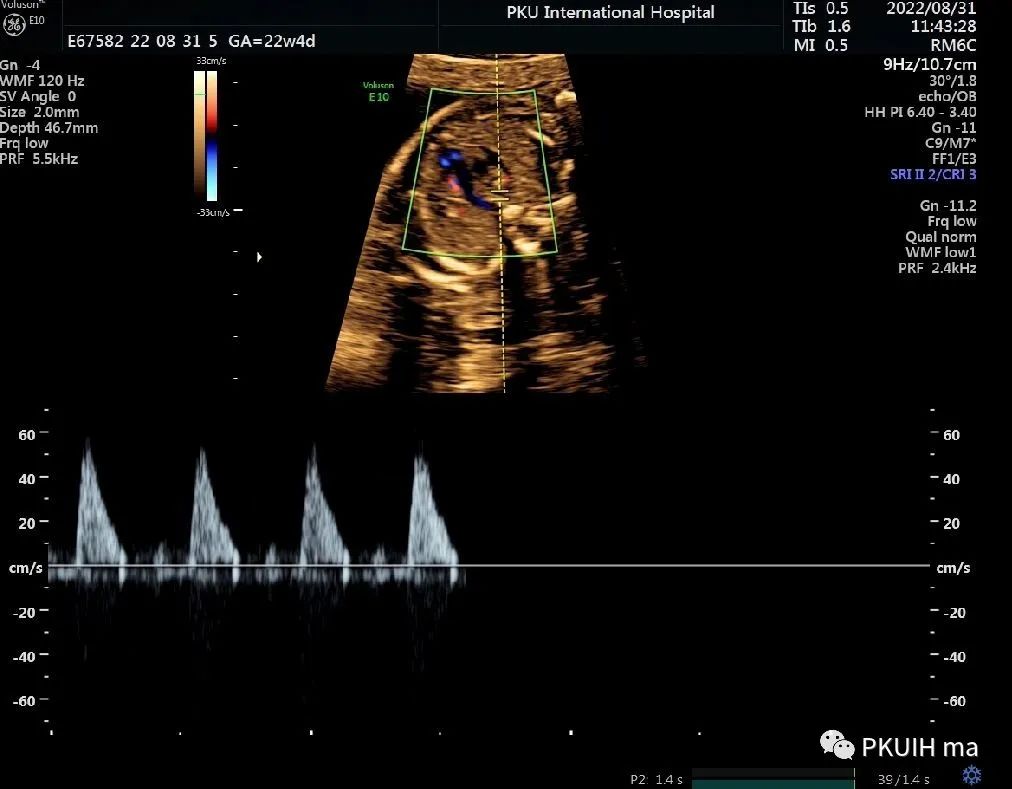

锁骨下动脉观察一般在主动脉弓水平横切面观察,显示左右锁骨下动脉像弓箭样向左右肩部走形。对于迷走的锁骨下动脉观察需要在三血管气管切面和主动脉冠状切面观察。右锁骨下动脉迷走在三血管气管切面可见一血管于主动脉弓降部发出自脊柱前方气管后方向右肩走行,在主动脉冠状切面显示主动脉弓降部见一血管迂曲向右肩部走行,频谱显示为动脉频谱。右锁骨下动脉迷走在三血管气管切面要和左无名静脉鉴别,左无名静脉汇入上腔静脉,频谱为静脉频谱,同时右锁骨下动脉也要和走形于气管后方汇入上腔静脉的奇静脉相鉴别,血流频谱有助于两者鉴别。

脊柱前方一红色血管为迷走的右锁骨下动脉,频谱为动脉频谱

ARSA较多见,常认为是一种正常的变异。超声很容易诊断,观察时建议把血流标尺降到15-20cm/s,也可以采用三维超声多平面观察或四维血流显像模式辨认。发现右锁骨下动脉迷走时建议做心内外系统全面扫查。单纯的锁骨下动脉迷走如果不合并染色体异常一般无临床意义,出生后预后良好。由于单纯锁骨下动脉迷走不形成完整血管环,临床上常无明显症状,仅有极少数病例报道患儿有吞咽困难或呼吸困难。迷走的右锁骨下动脉还可能会压迫喉返神经,导致神经麻痹,这种情况称为 Ortner 综合症。因此,临床中发现锁骨下动脉迷走时要注意观察迷走的血管与气管和食管的关系,食管后型最常见(80%),其次是气管、食管间型(15%),最后是气管前型(5%)。ARSA合并21-三体有文献报道,同时ARSA也出现在其他一些染色体非整倍体异常中;同时ARSA也可合并一些心脏的锥干畸形,此时要注意22q11微缺失的染色体异常风险。